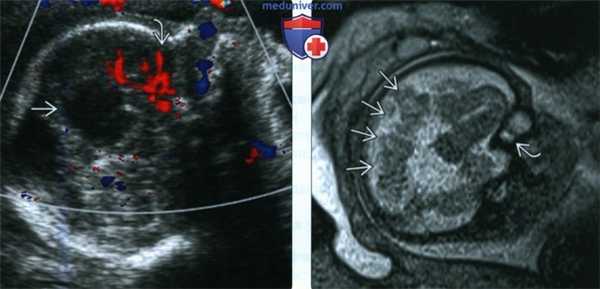

(Слева) УЗИ по средней линии. У плода с АМТ и внутричерепной кистой определяется патологическое ветвление передней мозговой артерии. У плодов со структурными изменениями головного мозга необходимо всегда оценивать строение глазных яблок.

(Справа) МРТ плода женского пола в III триместре, Т2-ВИ. Подтверждена АМТ (обращает внимание радиальное расположение извилин, а также впервые обнаружена колобома, что позволило заподозрить синдром Экарди. Офтальмологическое обследование новорожденного подтвердило диагноз.

(Слева) При МРТ Т2 FS в аксиальной проекции визуализируется уменьшенное левое глазное яблоко с обширной задней колобомой. Непосредственно позади глазного яблока в жировой клетчатке глазницы определяются две отдельные сопутствующие колобоматозные кисты.

(Справа) У младенца с множественными врожденными аномалиями при MPT Т2 FS в аксиальной проекции в заднем полюсе деформированного глазного яблока малых размеров определяется мелкий колобоматозный дефект. Видна крупная сопутствующая ретробульбарная киста.